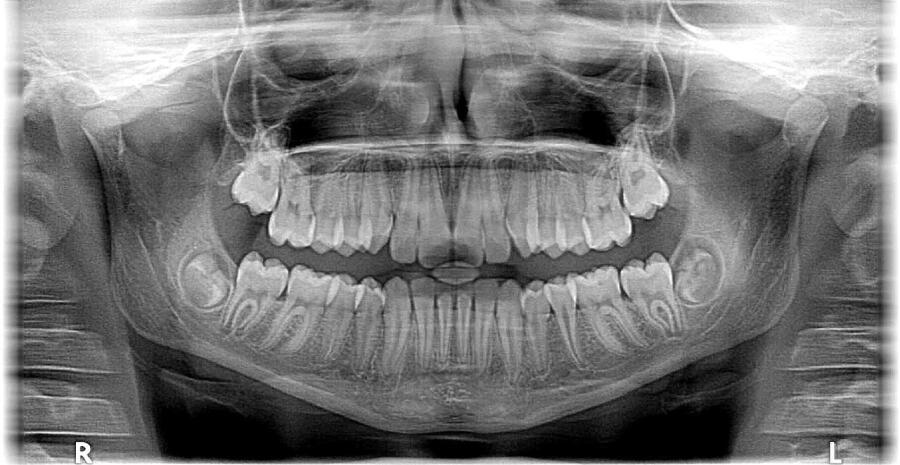

Какую помощь врачу могут оказать методы рентгеновских исследований? Рентген позволяет проводить неинвазивные исследования состояния внутренних органов, обнаружить на ранних стадиях всевозможные опухоли, поражения легких, уточняет положение костей при переломах и вывихах.

- Существует рентгенография — изображение фиксируется на специальной пленке прямым попаданием рентгеновских лучей.

- При различных видах рентгенографии больной получает от 0.2 до 1.6 мЗв (наибольшая доза — при просвечивании кишечника).